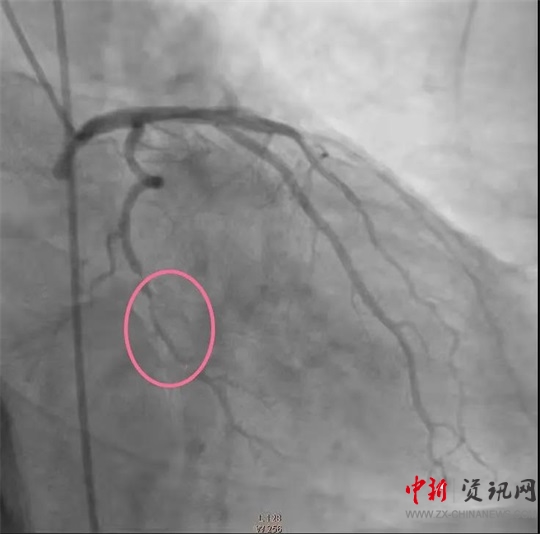

經(jīng)過一系列的術(shù)前準(zhǔn)備并經(jīng)患者家屬同意后,立即繞行病房進(jìn)入介入手術(shù)室,實(shí)施緊急手術(shù)。卒中中心團(tuán)隊(duì)、胸痛中心團(tuán)隊(duì)和介入團(tuán)隊(duì)密切配合,為患者分別實(shí)施了腦動(dòng)脈造影+主動(dòng)脈弓造影+顱內(nèi)動(dòng)脈瘤栓塞術(shù)+冠狀動(dòng)脈造影術(shù)+經(jīng)皮冠狀動(dòng)脈支架植入術(shù),成功把患者從死亡邊緣拉回。目前,患者病情穩(wěn)定,各項(xiàng)指標(biāo)良好。

(冠脈支架植入前)